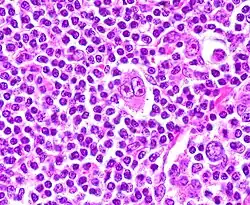

Клетки Березовского — Рид — Штернберга — атипичные многоядерные гигантские клетки, пролиферация которых характерна для лимфогранулематоза[1].

Чаще всего образуются из В-клеток, присутствующих в герминативном центре или покинувших его. Одной из особенностей этих клеток является высвобождение ими факторов, индуцирующих накопление реактивных лимфоцитов, макрофагов и гранулоцитов, составляющих обычно более 90 % общего количества опухолевых клеток. Типичной формой клеточной гибели для этих клеток является мумификация[2].

- Диагностические клетки: крупные (диаметром ≥ 45 мкм), много- или одноядерные, состоят из нескольких долей, содержащих «штампованные» ядрышки размером 5-7 мкм, имеют обильную цитоплазму.

- Мононуклеарные клетки: содержат одиночное ядро с большим, похожим на включение ядрышком.

- Лакунарные клетки: содержат складчатое или многодольчатое ядро, обильную бледную цитоплазму, которая часто утрачивается в процессе приготовления срезов и ядра остаются в пустой полости (лакуне).

- Лимфогистиоцитарные клетки: имеют полиплоидные ядра, плохо различимое ядрышко, умеренно обильную цитоплазму («кукурузные» клетки).